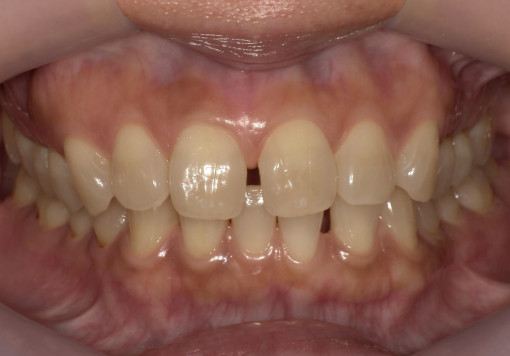

- 主訴:前歯のガタつき・上下の歯並びの不均一を改善したい。

根管治療途中の歯を治したい - 治療内容:マウスピース型矯正装置(SureSmile)による全顎矯正。

下顎1本インプラント埋入 - 治療期間:約36ヶ月

- 診断結果:

・上下顎に叢生を認め、特に上顎前歯部の位置不良が強い状態。

・噛み合わせのズレがあり、審美性・機能性の改善が必要と判断。

・抜歯を伴わないマウスピース矯正での改善が可能と診断。

歯根破折 - 治療後経過:

・前歯部の配列が整い、正中・噛み合わせが改善。経過も良好。 - 治療費用:マウスピース矯正(SureSmile):88万円税込

インプラント45万円税込

※症例により費用は前後します。

リスク・副作用:

・歯の動きに伴う痛み・違和感が数日出ることがあります。

・装着時間が不十分な場合、計画通りに歯が動かないことがあります。

・矯正後に保定装置を適切に使用しないと後戻りの可能性があります。

・虫歯・歯周病がある場合、先に治療が必要となる場合があります。